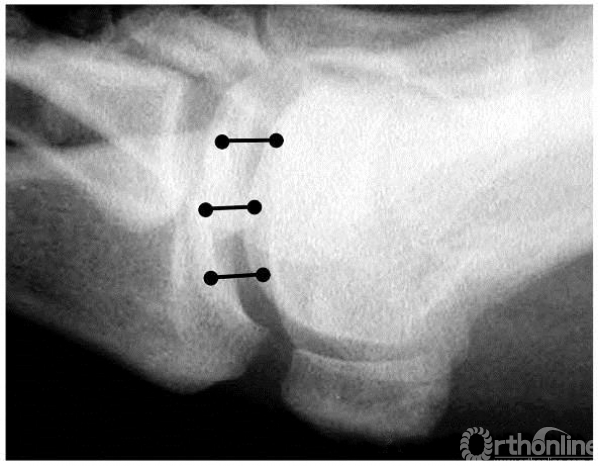

关节间隙测量方法

正位X线上:选择两端关节面的内侧、中间、外侧三点,分别连线

侧位X线上:选择两端关节面的背侧、中间、跖侧三点,分别连线

取上述六个连线长度平均值,即为关节间隙大小